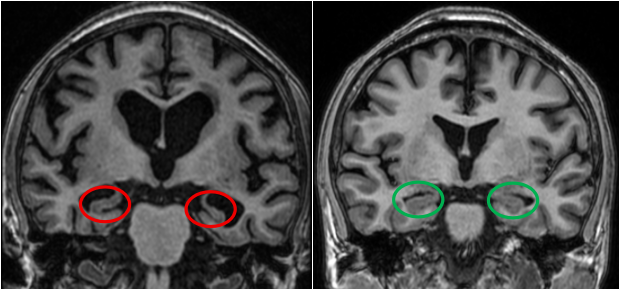

图2:头颅冠状位MRI图像(左图为56岁老年痴呆症患者,MTA4分,红色圆圈标注为明显萎缩的海马结构;右图为60岁健康成人,MTA0分,绿色圆圈内为正常海马结构)